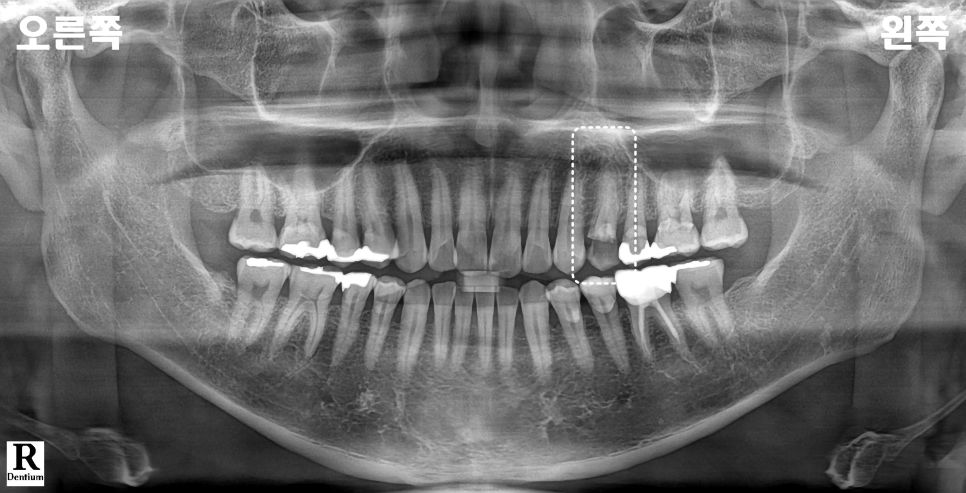

촬영일 : 250901

파노라마와 구내 사진, 탐침 검사로 확인하니

손상이 생각보다 컸고

충치가 깊이 진행되었어요.

근관치료부터 시작했어요.

촬영일 : 250901 / 250915